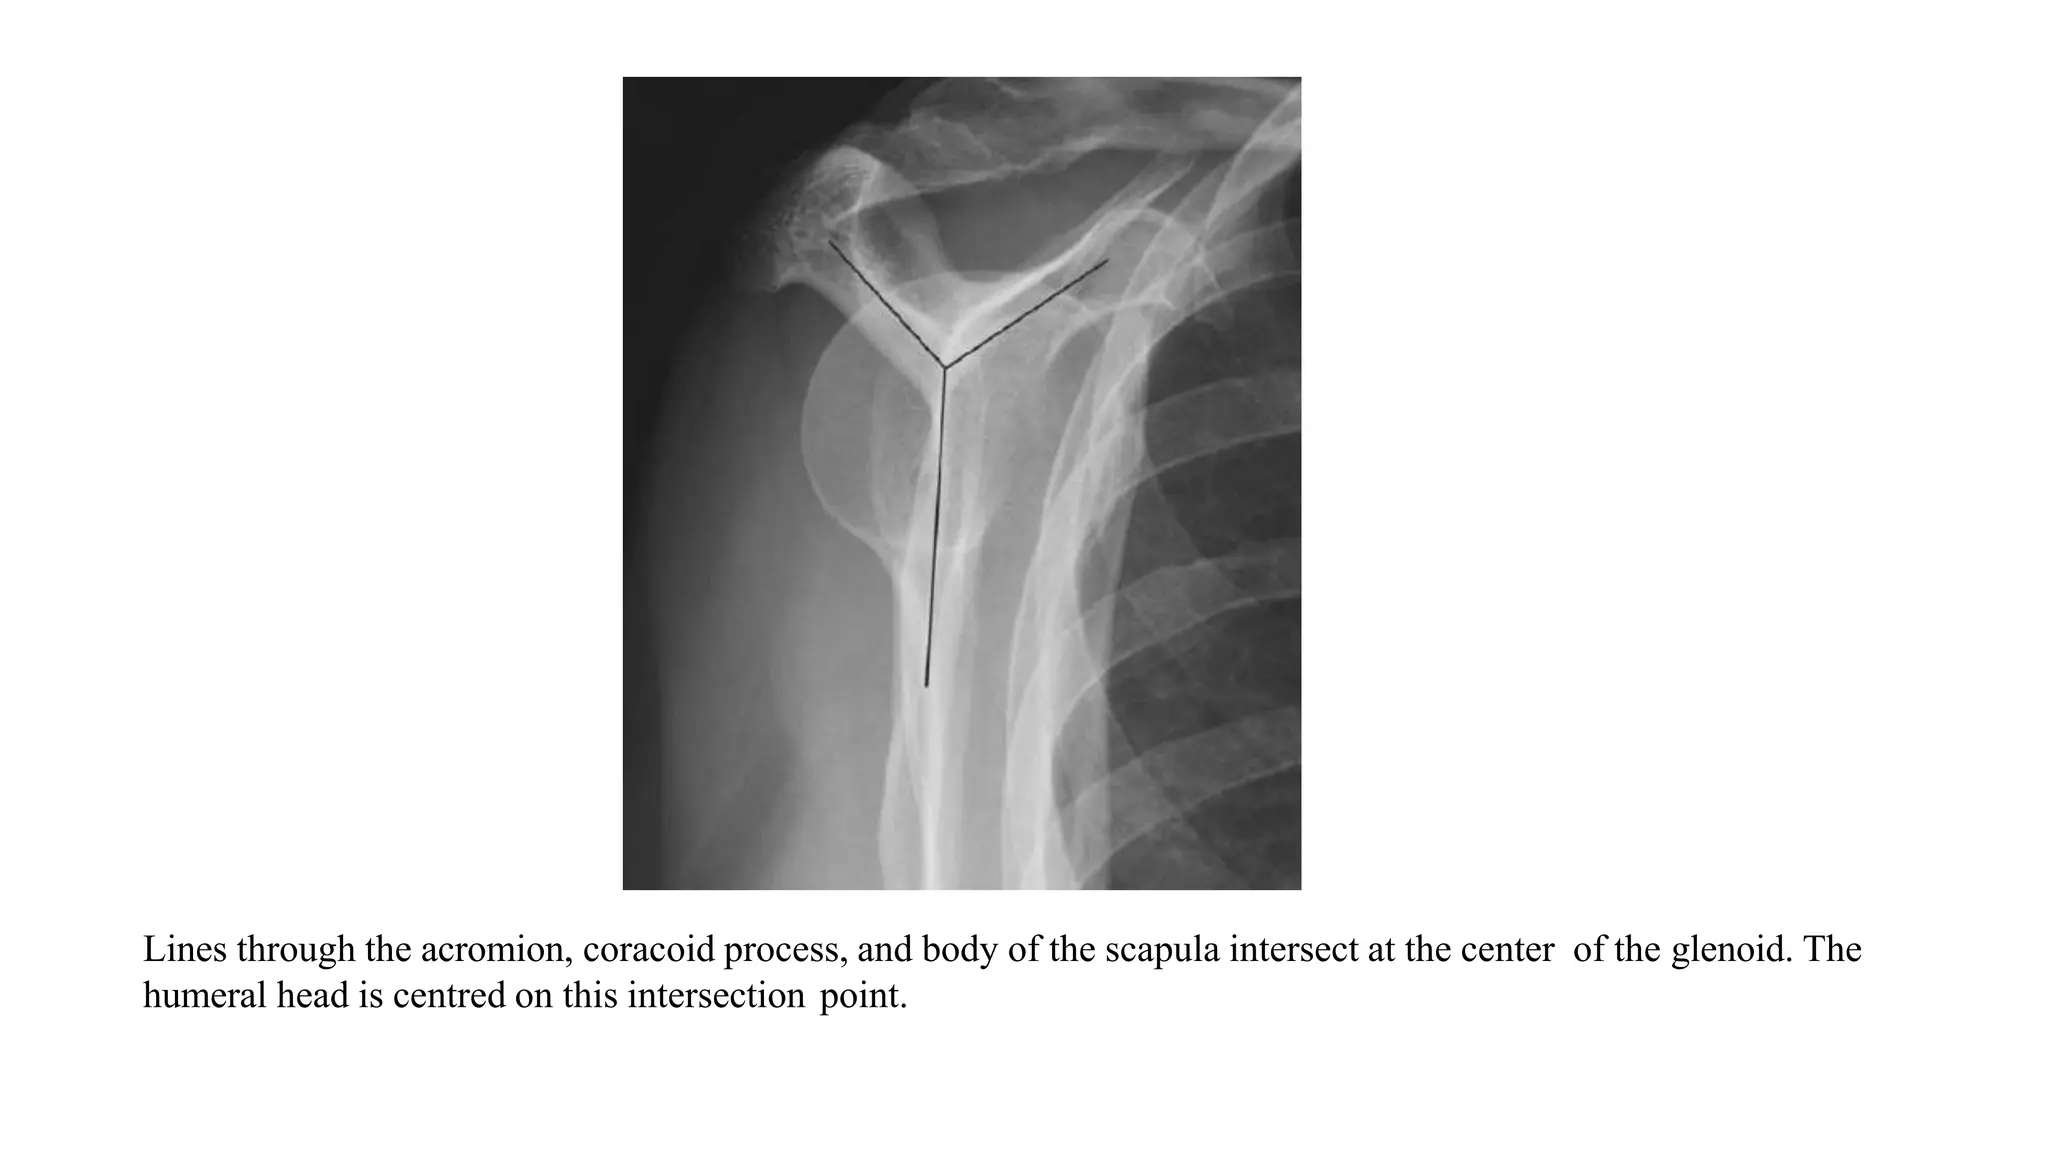

Lines through the acromion, coracoid process, and body of the scapula intersect at the center of the glenoid. The

humeral head is centred on this intersection point.